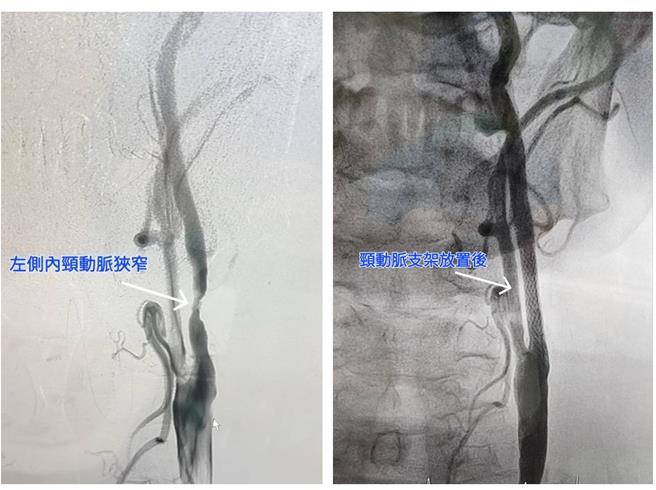

60歲的周姓男子有抽菸習慣,雖有高血壓卻未服用藥物控制,日前突然出現左眼視線一片黑及表達能力變差的症狀,經赴苗栗大千醫院檢查,顯示為左頸動脈高度狹窄。病人經醫師進行頸動脈支架置放術後,皆改善症狀、順利恢復出院,周某還同步進行冠狀動脈氣球擴張術,讓中風與心臟疾病的症狀同時獲得改善。

另1位88歲的李姓老翁,本身有高血壓病史且曾接受過心臟及左腳動脈支架置放,因連續三天出現右側手腳無力、意識不清、無法言語等情況,而到急診就醫,檢查確認為左側頸動脈高度狹窄,合併左腦灌流不全,因此出現中風症狀。經醫師進行頸動脈支架置放術後,皆改善症狀、順利恢復出院,

李亭儀解說,在頸動脈完全阻塞之前,常出現下列症狀:不明原因的昏厥、手腳無力發麻(尤其是半側的症狀)、暈眩、大舌頭等。當頸動脈阻塞較嚴重時,會引起半側大腦嚴重梗塞,還可能造成半側癱瘓、臥床等後遺症,甚至危及性命。如能在頸動脈尚未完全栓塞前,利用頸動脈超音波、電腦斷層、核磁共振、血管攝影等方法檢測出,在符合條件下,可進行頸動脈支架置放術,把狹窄的頸動脈撐開,增加腦部灌流,就可解決潛在的中風危機。

大千綜合醫院心臟血管內科醫師羅健賢表示,頸動脈狹窄基本的治療方法為藥物治療,但當狹窄嚴重時,則須考慮頸動脈內膜切除手術或現行的微創治療-頸動脈支架置放術。頸動脈支架置放術只需局部麻醉,由鼠蹊部的股動脈穿入,經由導管到達頸動脈狹窄處後,以氣球擴張並將支架固定於狹窄處。其喉返神經受損率及治療困難度比傳統的頸動脈內膜切除手術較低,且同樣能達到預防腦中風的效果,目前的頸動脈支架置放術再加上遠端保護裝置,更可以減少併發症,施行成功率超過95%以上。